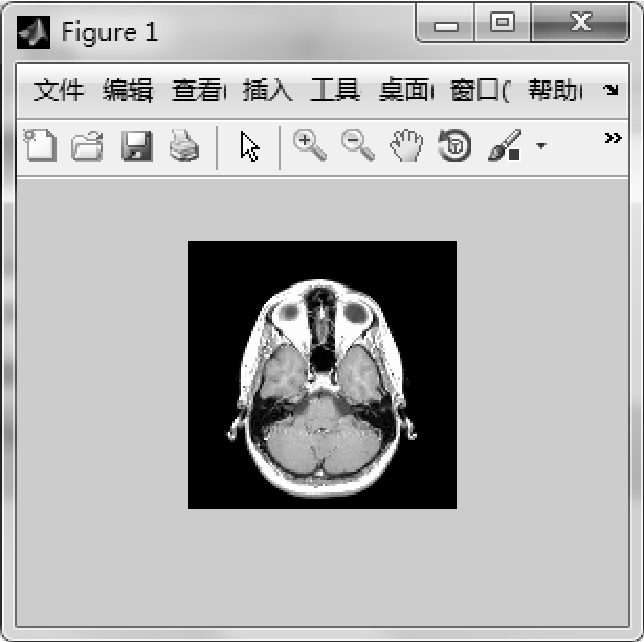

【实例1】 读取MATLAB自带的灰度图像。

图1.37 读取MATLAB自带的灰度图像